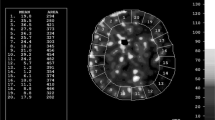

Xe-CT

In Xe-CT, inhaled stable xenon gas is used as a contrast agent [30]. Xenon is an inert, radiopaque gas that diffuses freely over the blood-brain barrier. A gas mixture with 28% xenon was delivered to the patient via the ventilator. After two unenhanced baseline scans, repeated scans of four 1-cm-thick slices with 1-cm gap were done during the wash-in phase of xenon. Quantitative CBF values were calculated from the dynamic changes in attenuation via a modified Kety-Schmidt equation. A system with a mobile CT scanner was used, which enables CBF measurement to be done bedside at the NICU. This was considered an advantage since severely ill patients may be impossible to transfer from the NICU for CBF measurements. The measured CBF values probably also better reflect the values during neurointensive care, rather than values measured at the radiology department, where ventilation and sedation parameters are likely to be different.

From the CBF raw data, three parameters were derived:

-

Mean global cortical CBF

-

Percentage of global cortical volume with CBF <20 ml/100 g/min (CBF% <20)

-

Percentage of global cortical volume with CBF <10 ml/100 g/min (CBF% <10)